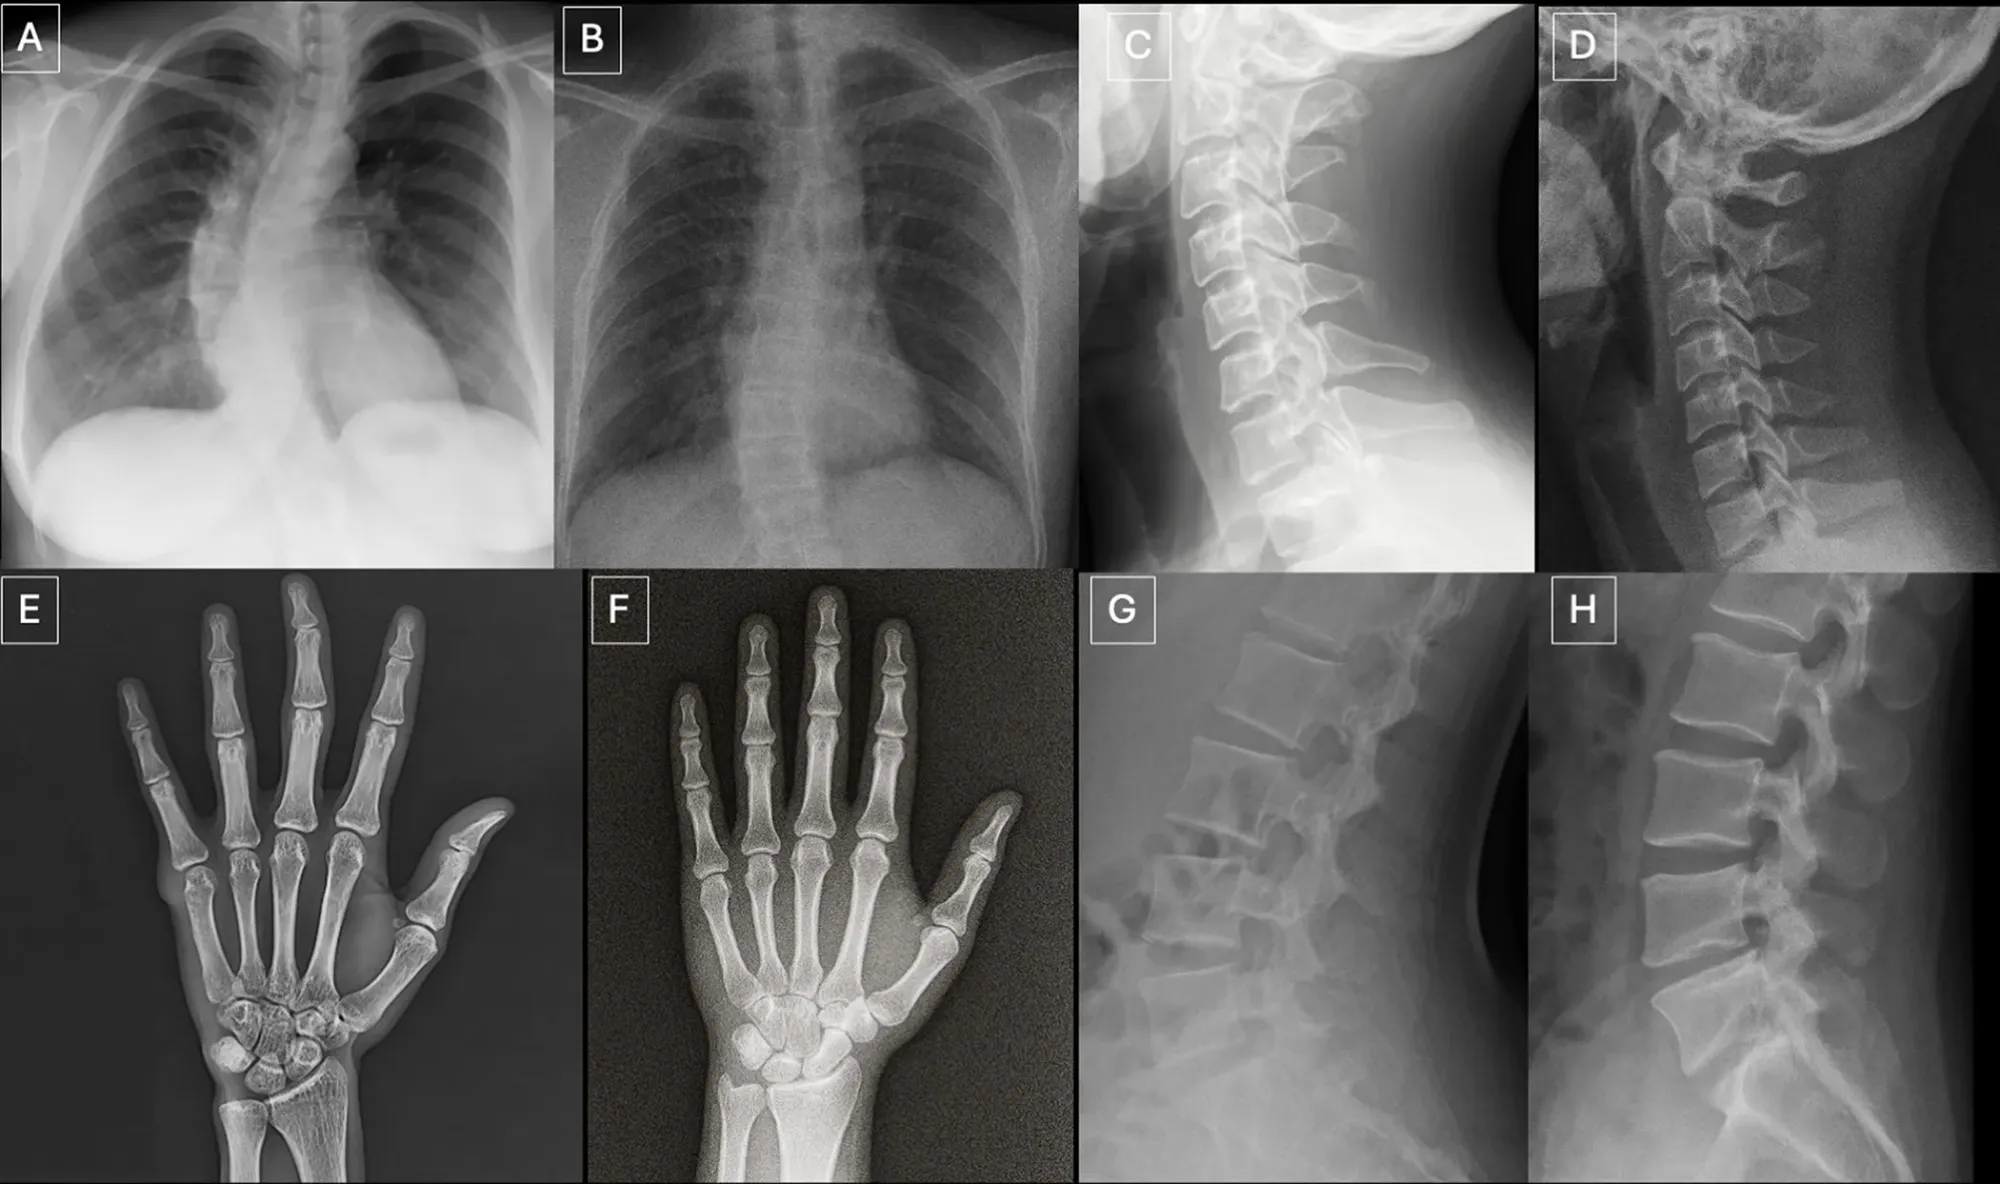

根據呢份由 Mickael Tordjman 醫生及其團隊進行嘅回顧性診斷準確度研究,AI 系統目前已經可以根據簡單嘅文字指令,無中生有咁生成出包含各種病理特徵(例如骨折、腫瘤、感染等)嘅 X 光片。為咗測試人類同機器對呢啲假相嘅辨識能力,研究團隊邀請咗來自六個國家嘅 17 位放射科醫生參與測試,同時亦安排咗四款主流嘅 AI 模型進行評估。結果發現,喺唔知道有假相混入嘅情況下,只有 41% 嘅醫生主動察覺到有異樣;而即使喺被明確告知有 AI 生成影像存在之後,醫生嘅平均分辨準確率亦只得 74.8%。換言之,每四張 AI 假相入面,就有一張成功瞞天過海。

實驗分為三個階段進行。喺第一階段(盲測階段),醫生並唔知道研究嘅真正目的,佢哋需要為 154 張不同部位嘅 X 光片(當中 77 張係真實臨床影像,另外 77 張係由 GPT-4o 生成嘅假相)進行影像質素評分同診斷。結果顯示,醫生對真假相片嘅質素評分相當接近,而且只有 7 名醫生(約 41%)自然咁發覺部分相片有古怪,懷疑係由 AI 生成。

- 過度完美嘅對稱性:人體結構喺現實中總會有些微嘅不對稱,但 AI 往往會生成出好似倒影一樣、左右完美對稱嘅影像。例如肺部兩側嘅紋理過於一致,或者脊椎骨排列得太過筆直(除非喺指令中特別要求加入脊柱側彎)。

- 骨頭表面過於平滑:真實嘅骨骼邊緣通常會有自然嘅微小凹凸或不規則特徵(例如腰椎嘅 Schmorl 結節)。而 AI 畫出嚟嘅骨頭,皮質骨厚度往往均勻得唔自然,骨折線亦經常顯得太乾淨、太平滑,甚至只係出現單邊皮質骨折斷嘅不合理情況。

- 統一而呆板嘅雜訊分佈:真實嘅 X 光片會因為設備同人體組織密度而產生不同程度嘅顆粒感。但 AI 生成影像嘅雜訊模式通常會呈現出完全一致、均勻分佈嘅狀態,缺乏層次感。

- 軟組織細節缺失或唔自然:AI 有時會忽略咗一啲微小但必要嘅解剖細節,例如手部 X 光片入面會無端端缺少咗指甲床嘅陰影,或者植入嘅醫療金屬器材邊緣異常鋒利。